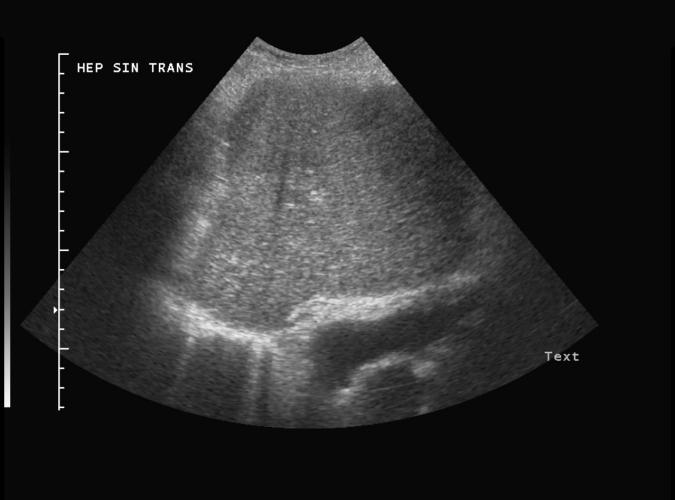

Patologi.

Trans. Diskret fokal förändring ventalt i vänster leverlob hos en patient med levercirrhos. Vidare utredning visade

hepatocellulär cancer. se bild 2h, long bild.